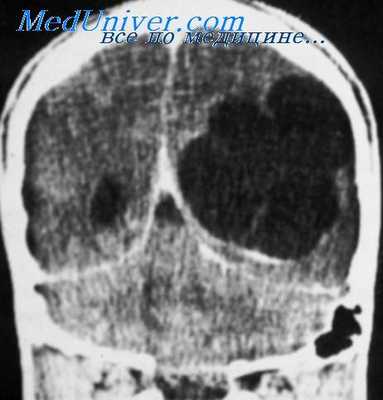

В последнее время все большее клиническое применение находит КТ. Несмотря на высокую разрешающую способность метода, частота выявляемых им изменений меньше, чем обнаруживаемых при ПЭГ, — от 33 до 54%. Ценной в диагностической отношении КТ оказывается у больных парциальной эпилепсией (изменения выявляются в 62,5% случаев).

Современные методы исследования высокоразрешающей способности (КТ, позитронная эмиссионная томография) ие подтверждают наличия арахноидита при эпилепсии. Из 36 наблюдавшихся нами больных эпилепсией, подвергнутых КТ, кистозно-слипчивый процесс в оболочках ие был обнаружен ни у одного.